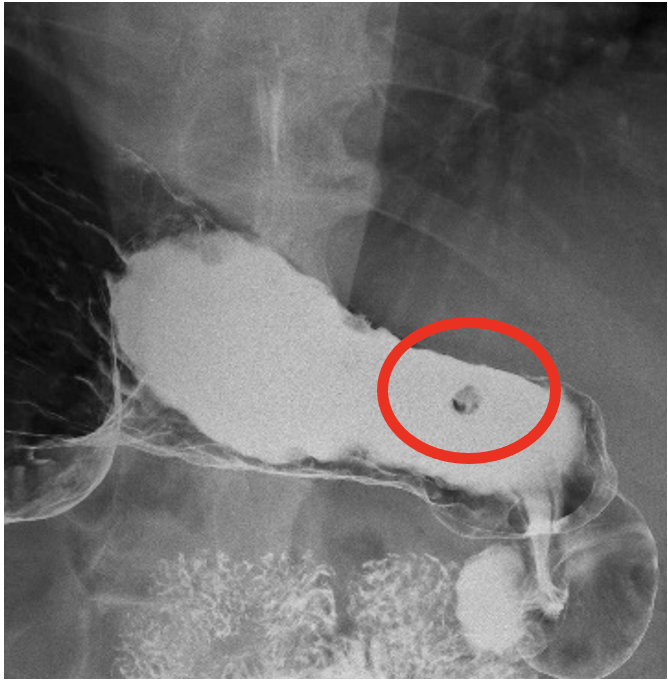

慢性期病院でありながら、最新鋭の64列CT装置・レントゲン装置(FPD)・X線TV装置・骨密度測定装置(DXA)などを取り揃えており、高い医療技術で皆様の診療の手助けをさせていただきます。